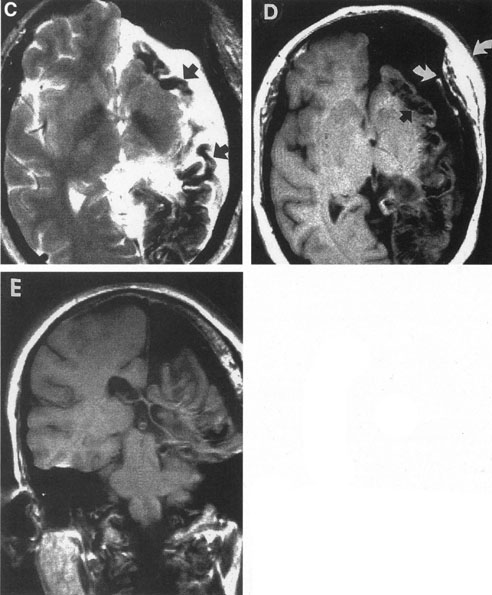

The therapy for AVMs has been reviewed elsewhere.91–93 The preferred treatment remains complete surgical excision of the malformation. However, significant advances in endovascular and radiosurgical techniques have resulted in a marked increase in the use of multimodal, staged approaches to AVM treatment. A variety of intravascular techniques use embolization91 with materials such as particles of polyvinyl alcohol (PVA), platinum coils, and injection of liquid N-butyl-cyanoacrylate (NBCA) adhesive (Fig. 11). Complications of intravascular embolotherapy include vessel perforation by the catheter, migration of embolic materials, and infarction and hemorrhage of normal brain.

Fig. 11. Embolization of middle cerebral vessels that supply occipital lobe arteriovenous malformation (AVM). The patient had a subarachnoid and intraparenchymal hemorrhage that produced a left homonymous field defect. A: Right carotid arteriogram demonstrates contribution via posterior communicating artery to a right occipital lobe AVM. B: Vertebral injection. The arrow points to the enlarged right posterior cerebral artery that is a major feeder of the AVM. C: Right carotid arteriogram during glue embolization procedure. The arrow points to a catheter as it traverses the segment seen in (B). The catheter was advanced via the internal carotid artery but is positioned far posteriorly. D: Upper branches to the AVM now are occluded, with residual low-flow vascularization via the middle cerebral artery. E: Skull film showing radiopaque glue within the AVM and blood vessels previously supplying it. The patient had a persistent visual field defect but greatly reduced headache and no persistence of subjective bruit. (Courtesy of Dr. Joseph Horton.)